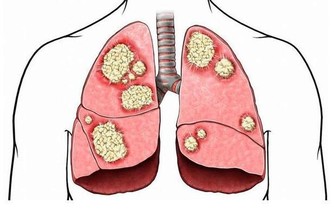

堅持刷牙許多老年人認為沒了牙,刷牙也就成畫蛇添足之舉了。其實不然,刷牙不僅限於保持牙齒衛生,預防蛀牙,對整個口腔乃至鄰近器官都有保健作用。

刷牙還可防止老年性肺炎的偷襲,奧妙在於刷牙時牙刷刺激牙齦、牙槽,引起興奮傳入中樞神經系統,可使吞嚥反射和咳嗽反射功能增強,防止口腔中的異物錯吸入呼吸道而誘發吸入性肺炎。